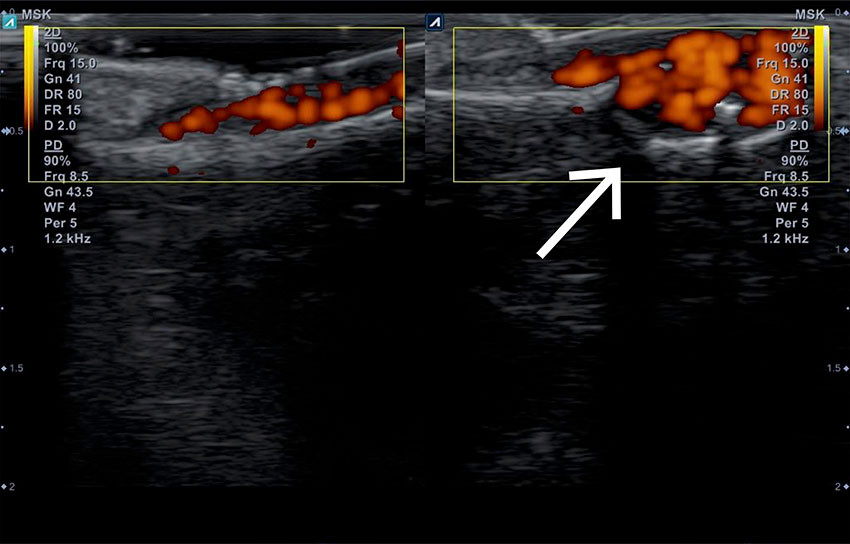

Spesialist i nevrologi fant ingen sikker nevrogen årsak, men ultralyd av venstre tommel viste en lobulær struktur med økt vaskularisering under neglen (figur 2). Kvinnen ble derpå henvist til håndkirurg. Som ledd i den kirurgiske vurderingen ble det tatt røntgen, som viste cyster i tommelens ytterfalang. Sammen med funn på påfølgende CT, MR med kontrast og ultralyd konkluderte man med en sannsynlig 6 × 6 mm stor subungual glomustumor. Dette ga sammen med hennes kliniske symptomer og tegn indikasjon for operasjon.